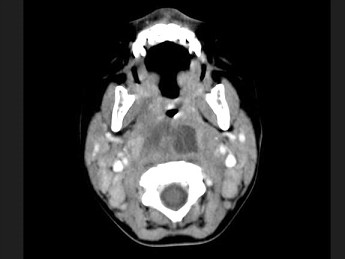

18.10个月大的婴儿,发热,曾患中耳炎,CT扫描如图所示,请选择正确的描述或诊断 ( )![]() ![]() ![]() |

| 正确答案:ABCD |